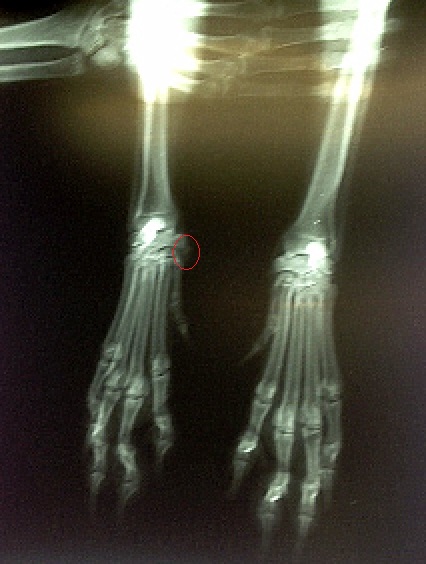

Beletelt egy kis időbe, míg Zalán kijött az eredményekkel, majd felhelyezte a megvilágító testre (biztos van ennek is valami hivatalos neve…) Vészhelyzet című filmben éreztem magam, majd várakoztunk, várakoztunk és várakoztunk. Viccesen megkérdeztem Zalán feleségétől, hogy ez mindig ennyi ideig szokott tartani, mert a doktor úr bevonult egy szobába miután kihozta a felvételeket. Jaj majd meghaltam, hogy megtudjam, jó amit látok vagy sem… mert persze odasomfordáltam, hogy megnézhessem őket közelebbről is. Készítettem képet, bár elég rossz minőségű lett, szidom is magam érte… :/ A lényeget bekarikáztam, akinek jó a szeme az látja, azt ha összehasonlítjátok a másik lábbal megvan a különbség. Segítek, mert tényleg nem látszik. Szóval a jobb oldalon meg van duzzadva az a rész, alig látszik a felvételen is amúgy, de azért szemléltetésnek jó.

Jamie röntgenje